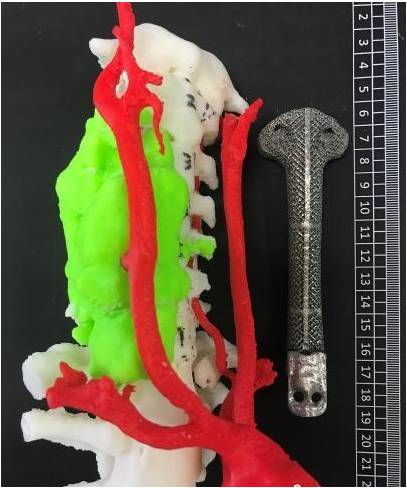

ANYTHINK 经导管主动脉瓣膜置换术分析系统